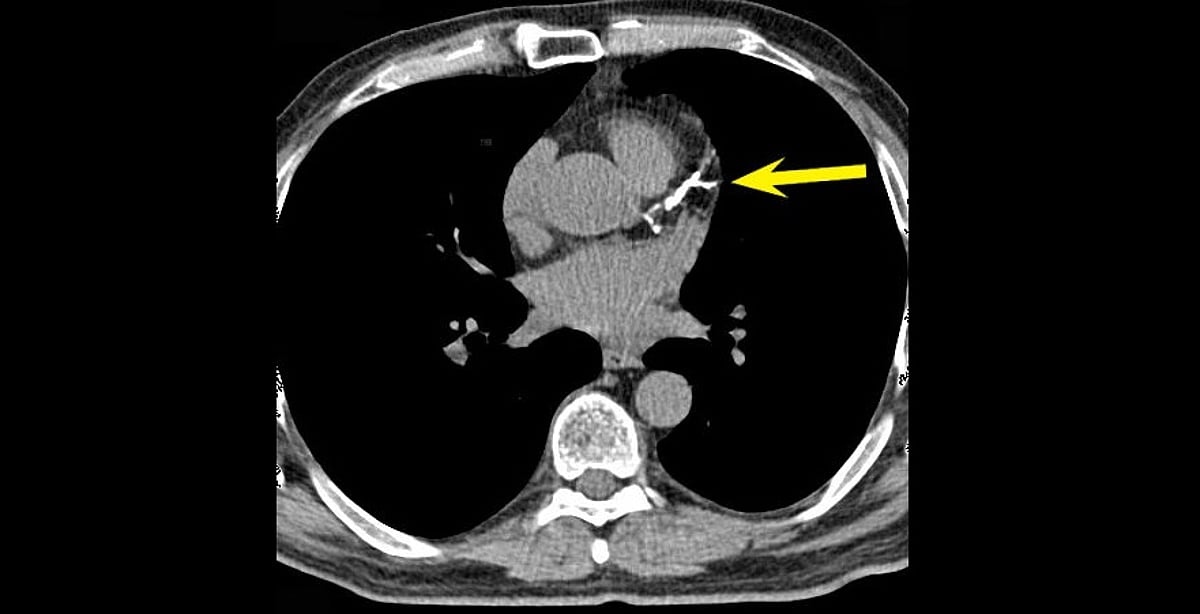

"النمر": تكلّس الشرايين قد يرتفع 25٪ سنويًّا دون خطورة.. واستخدام الأسبرين مشروط بـ3 عوامل